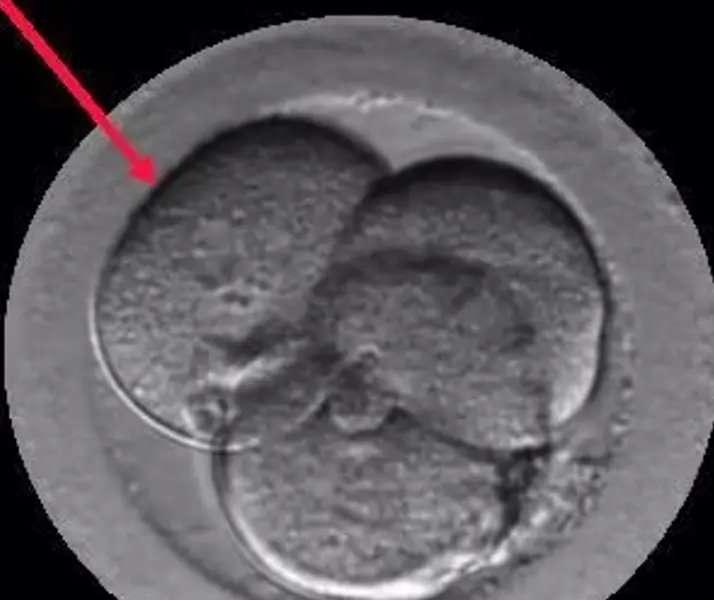

<p> Embrión Multinucleado. - Institut Marquès </p>

El Dr. Borja Marquès es el autor del estudio "Signos de auto-reparación de los embriones en el laboratorio de FIV" cuyas conclusiones apuntan que los embriones poseen un mecanismo de auto-corrección ignorado hasta hoy. Según este trabajo que se presenta esta semana en Murcia, en el 36º Congreso de la Sociedad Española de Ginecología (SEGO), embriones que han sufrido división reversa (desaparición de alguna de sus células) o multinucleación (presencia de dos o más núcleos en alguna de sus células) pueden acabar con éxito, es decir, con un embarazo normal y el nacimiento de un bebé sano.

Gracias a los incubadores con cámaras time-lapse (Embryoscope), en los laboratorios de Institut Marquès ha sido posible captar las imágenes de embriones con división reversa reabsorbiendo sus propias células y de embriones multinucleados expulsando las células anómalas en el 4º o 5º día de vida. Para conseguirlo, se ha analizado el desarrollo de 21.274 embriones, desde su fecundación hasta que llegaron a blastocisto.